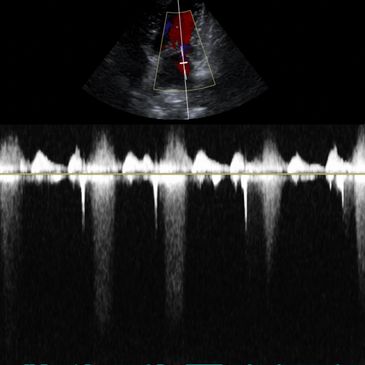

In-house laboratory, x-ray, ultrasound and echocardiogram are available in our veterinary hospital.